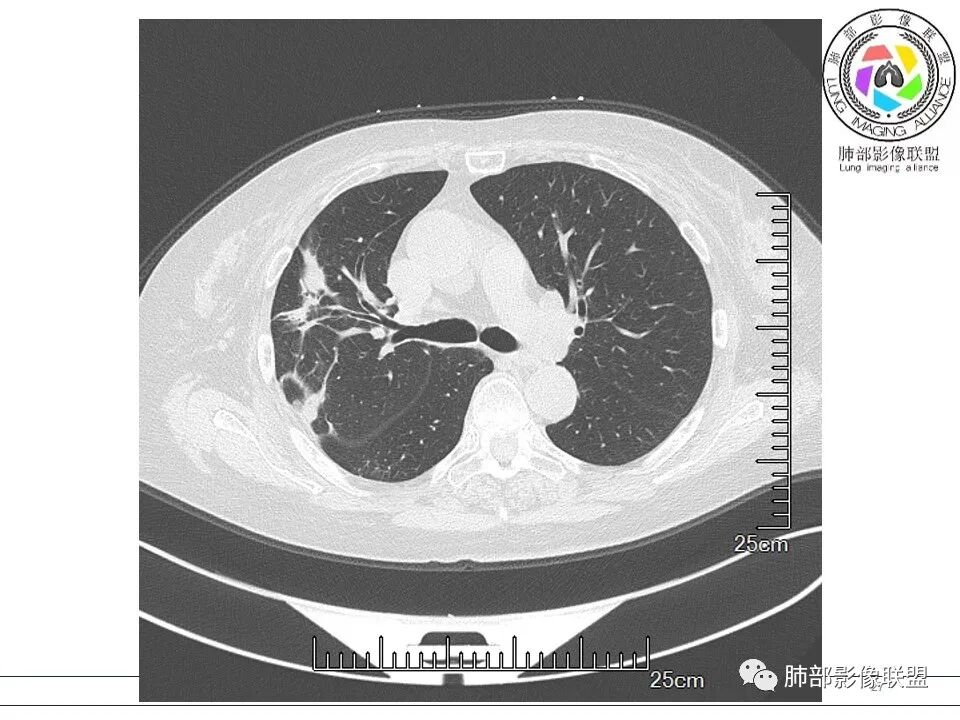

放射小白: 晨读病例:女性,70岁,风湿性多肌痛病史,右肺见不规则结节,边缘及周围见纤维索条影,考虑OP,药物性肺损伤。

谢加平: 右肺上叶外周,近胸膜下结节病灶,侧向融合,边缘清,见平直边,与胸膜平行分布,支气管进入略扩张,周围见多发长索条影,方向肉芽肿性炎症,建议隐球菌荚膜抗原检查,肿瘤不支持,经皮肺穿刺病理检查!

红日初升: 胸膜下结块,平行胸膜,收缩力较强,肉芽肿样边缘,考虑炎性,小卫星灶、似有凝固性坏死,隐球>op

小兜: 晨读,女,70岁,风湿性多肌痛病史一年,半月前体检发现肺部阴影,无症状,口服药物治疗。现片示:右肺胸膜下条形实变影,局部层面似见多结节融合,周边伴条索影。下方近叶间胸膜处斑片状实变影伴条索影,宽基底与胸膜相连。综合考虑为炎性病变,隐球菌或OP可能

宇宙: 右肺上叶胸膜下结节,多结节融合,长轴平行胸膜,边缘模糊,周围长索条,胸膜牵拉,近端支气管充气扩张,考虑隐球菌,鉴别OP

看图说话: 右肺上叶外胸膜下结节,边缘清,密度均匀,边缘长索条,支气管壁增厚,进入略扩张,胸膜牵拉,考虑机化性肺炎,隐球。

玫: 晨读:右肺上叶胸膜下软组织密度影,边缘模糊,周围见条索影及少许磨玻璃影,轻度胸膜牵拉,考虑炎性病变。

金豆 (刘权威): 右肺上叶胸膜下团块,支气管充气征,边缘纤维索条,磨玻璃,OP。

黄棘: 右肺上叶近胸膜下病灶,多个融合,边缘清,与胸膜平行分布,支气管进入后堵塞,周围见多发长索条影,考虑隐球菌

果哣.: 右肺上叶靠近胸膜结节影,平直为主,边缘清晰,支气管进入后截断,有扩张,考虑炎性隐球菌可能

丽: 晨读,老年女性,右肺上叶不规则病灶,边缘多发长索条,支气管穿行达病灶远端,常规抗炎无明显吸收,考虑炎性病变,隐球菌可能大

衡妈: 老年女性,右肺上叶沿胸膜下不规则实性病灶,长轴平行于胸膜,有结节融合感,边缘部分彭隆部分平直,周围可见数条纤维灶影,病灶内可见充气支气管征未达远端,首诊考虑慢性炎性肉芽肿,隐球菌?机化性肺炎?建议增强扫描及ct下穿刺活检。

放射线 (王秀仙): 右肺上叶胸膜下结节样影,边缘平直收缩,胸膜牵拉,支气管进入病灶并扩张,部分支气管进入后阻塞,长轴平行于胸膜,周围可见片状及条索状影,隐球?机化性肺炎?

张延军: 病变与胸膜平行,近端见气管进入,口服激素治疗史 考虑隐球菌感染 伴OP样改变

晨读:女,70,未诉症状。风湿性多肌痛病史,口服强的松等药物治疗。胸部CT:右肺上叶多发不规则斑片影,沿支气管分布,部分病灶侧向融合、平行于胸膜,边缘平直内收为主、部分彭隆,周围模糊晕、可见数条纤维灶影,胸膜牵拉,病灶内可见充气支气管征、管腔不畅,考虑慢性炎症,PC?OP?鉴别腺Ca、SCLC等。

瑞欣 (刑瑞欣): 晨读,老年女性,右肺上叶不规则高密度影,可见胸膜牵拉,边缘光滑平直,与胸膜平行,周围条状影,可见支气管充气征,有风湿病史,考虑机化性炎症,鉴别隐球菌,腺癌

良孑: 右肺胸膜下多发结节,长轴与胸膜平行,部分病灶有多结节融合,可见近端支气管充气征,有晕征及晕中软毛刺,长期口服激素病史,抗炎效果欠佳。病灶形态单一,无播散性树芽,结节内无支气管穿行,单侧发病,收缩力差,可排除TB,OP及淋巴瘤,综和考虑支持隐球菌

尘缘: 典型的隐球机化期改变

南边: 这个病例大方向没问题,炎性。目前大家都是考虑:隐球菌病、OP,其实这两个结论有重叠,而且这个病例很值得讨论,可惜,估计没有证实。影像特点:病灶长轴与胸膜平行,侧向融合特点明显,符合隐球菌病,问题是目前的状态,边缘收缩明显

内部支气管扩张,周围少量GGO,而且病灶离开了胸膜,附近长索条影,支持机化的改变